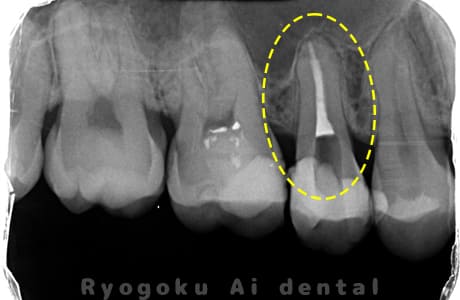

Case02

- 慢性根尖性歯周炎

- 治療期間

-

- マイクロエンド

- 治療費用

噛むと痛みが出る、とのことで来院した患者様です。他院での根管治療を終えてましたが、根尖病変を認めるため、マイクロエンドを行いました。